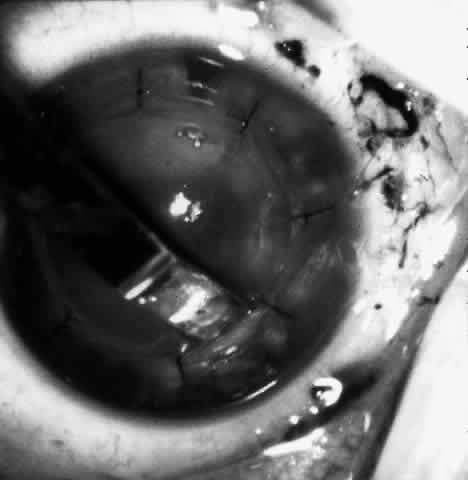

Next, an angled lamellar dissector such as one would use to dissect a trabeculectomy flap is used to create a 1-mm lamellar pocket in the peripheral direction for 360° around the cornea at the base of the trephined incision. In the past a small strip of cornea was excised centrally from the inner aspect of the trephine incision. This keratectomy has been found unnecessary and the procedure may be more easily reversed without the keratectomy. Then the tissue lens is draped over the cornea stroma-side-down and centered on the annular incision (Fig. 9).

Fig. 9. Hydrated lens is placed on the front of the cornea.